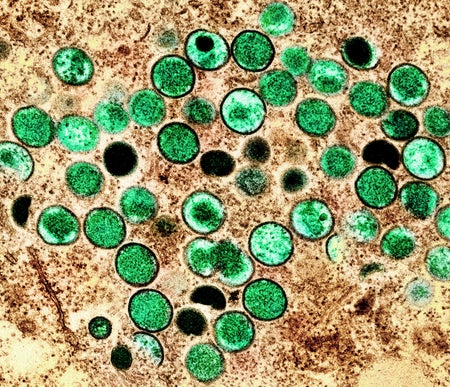

What Is Monkeypox, the Virus Infecting People in the U.S. and Europe?

A microbiologist explains what is known about this smallpox cousin